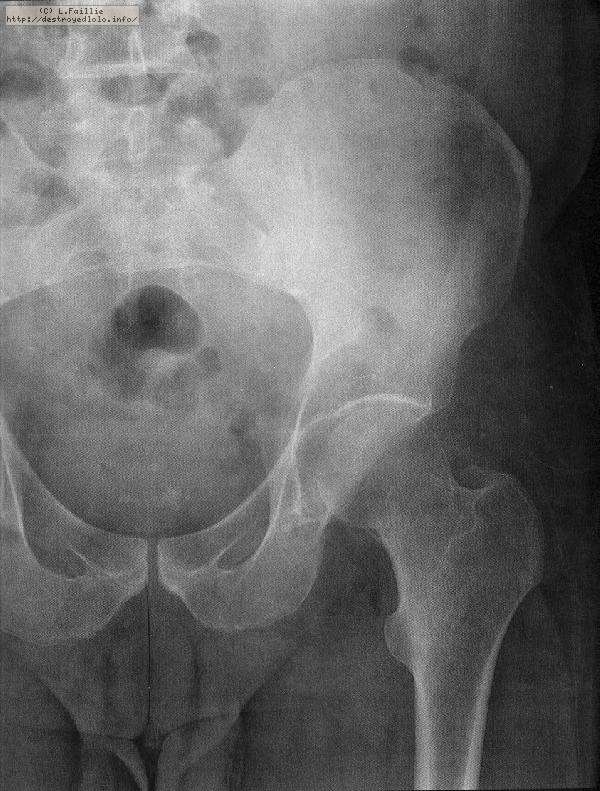

La saison est finie : fracture du col du fémur :(

Pompier, hôpital, 3 mois alités ...